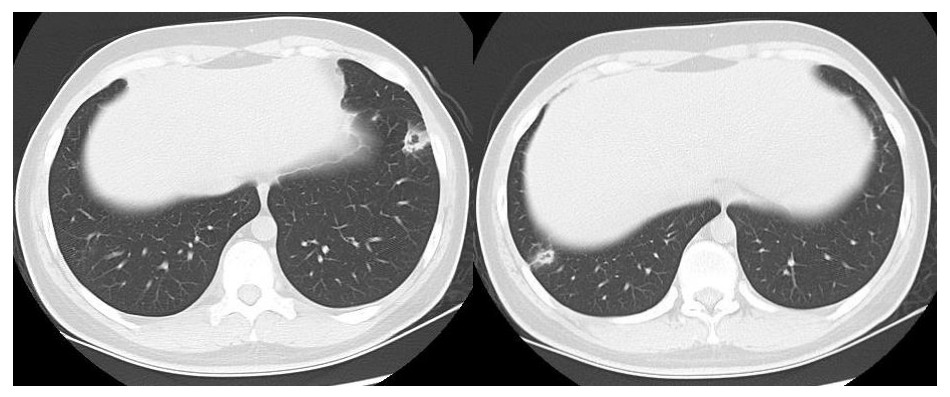

患者男性,21岁,主因“间断发热、寒战伴头晕头痛2周”于2021年11月18日急诊收入院。患者诉2周前进食烧烤后出现发热,体温最高可达42℃, 伴畏寒、寒战、咽痛、头晕、头痛、乏力,就诊于本院耳鼻喉科后,查体见扁桃体有脓点,快测降钙素原(procalcitonin,PCT)为37.27 ng/mL,胸部CT检查未见异常,考虑诊断为“急性化脓性扁桃体炎”,先后给予左氧氟沙星、阿奇霉素抗感染及甲泼尼龙控制炎症后上述症状未见明显好转,为进一步治疗,收入急诊病房治疗,既往体健,入院时查体:体温41℃,脉搏98次/min,呼吸频率23次/min,血压120/60 mmHg(1 mmHg=0.133 kPa),患者神志清楚,急性病容,精神较差,颈部浅表淋巴结触及肿大,右侧较大约2.0 cm ×0.5 cm,左侧较大约1.3 cm×0.7 cm,质软,活动度好,界限清楚,有压痛,表面皮肤无红肿,无破溃,双肺呼吸音清,未闻及干湿性啰音,心脏听诊无杂音,腹软,无压痛及反跳痛,双下肢无水肿。血常规检查白细胞计数10.49×109/L, 中性粒细胞百分比94.6%,血红蛋白120 g/L, 血小板计数107×109/L,PCT 42.83 ng/mL,白介素6(interleukin, IL-6)980.30 pg/mL,C反应蛋白211 mg/L,G试验、GM试验阴性。胸部CT检查示右肺上叶可见一单发实变影,其内可见空洞(图 1)。根据病史、查体和辅助检查考虑诊断为肺脓肿,给予注射用哌拉西林钠他唑巴坦4.5 g Q8h治疗,入院第2天,患者仍有发热,体温最高38.7℃,给予对症处理,入院第3天患者体温峰值有所下降,体温维持在37~38℃,考虑抗炎有效,痰培养结果回报为纹带棒杆菌,草绿色链球菌(奈瑟菌属),考虑这2种细菌为皮肤或口腔的正常菌群,为条件致病菌,该细菌导致发热的可能性较小,继续给予哌拉西林钠他唑巴坦治疗。入院第5天血培养回报血液中找到坏死梭杆菌,考虑为血流感染。加用甲硝唑1 g每8 h一次抗感染治疗,复查血常规白细胞计数8.14×109/L, 中性粒细胞百分比81.5%,血红蛋白120 g/L, 血小板计数246×109/L,PCT 3.43 ng/mL,IL-6 13.04 pg/mL,C反应蛋白5 mg/L,炎性指标较前明显下降,考虑抗炎治疗有效,继续目前抗生素治疗。入院第10天患者体温仍有低热,体温36.5~37.5 ℃,复查胸部CT见双肺多发小结节,双肺多发空洞病变,考虑炎性可能(图 2)。颈静脉超声检查提示患者左侧颈内静脉血栓形成,给予依诺肝素0.4 mL每12 h一次抗凝治疗,根据血培养结果、胸部CT表现和颈静脉超声结果,考虑该患者诊断为坏死梭杆菌导致Lemierre综合征(Lemierre syndrome, LS)。用哌拉西林钠他唑巴坦联合甲硝唑治疗后仍有低热,化验检查PCT为0.30 ng/mL,IL-6为3.52 pg/mL,C反应蛋白为3 mg/L,胸部CT示肺部空洞较前增加,考虑感染未完全控制,改为调整抗生素为比阿培南0.6 g每12 h一次联合甲硝唑1g每8 h一次抗感染治疗,治疗1周后患者体温恢复正常,CT检查示双肺多发空洞消失,残留少量索条影(图 3),患者病情好转出院,出院带药给予口服甲硝唑联合阿莫西林抗感染治疗,利伐沙班抗凝治疗,随诊2周后复查胸部CT正常。

| 空洞病变消失,残留少量实变及索条影 图 3 入院第19天胸部CT |